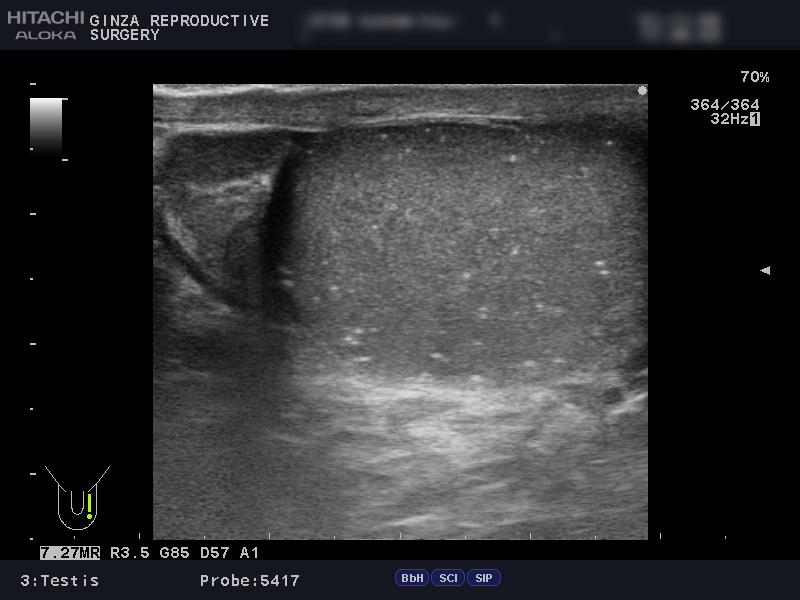

精索静脈瘤の診断には、エコー検査を用います。

エコー検査では、精巣内や精巣上体の観察と精索静脈瘤の診断を行います。同時に不妊や別の病気と関連している、以下のような異常がないかどうかも詳しく確認します。

以下は、当院でエコー検査を受けられた患者さんの画像です。

精索静脈径が3mm以上だと治療を推奨されるところ、左側の画像では4.5~6.8mmで、血管が明らかに拡張しています。

安静にしていてもドップラー法で顕著な逆流が観察でき、腹圧でさらに増強していました。ドップラー法は、血液の逆流を確認する方法です。

上の画像検査結果より、グレード3の左精索静脈瘤であると診断されました。